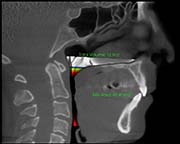

Pre Surgery

Surgical Plan